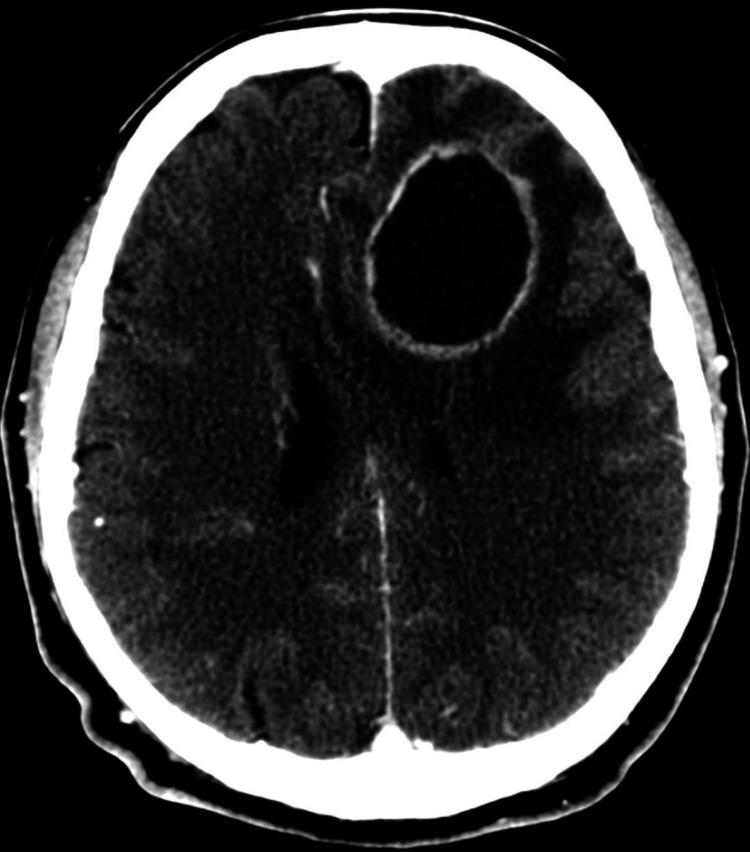

Tuberculosis is a disease caused by a bacteria named Mycobacterium tuberculosis (M. tb). It is estimated by World Health Organization (WHO) that nearly a quarter of the world's population is infected. Tuberculoma of the brain is one of the most severe extrapulmonary forms that affects patients younger than 40 years of age. Brain parenchymal tuberculoma develops in nearly one of 300 non-treated cases of pulmonary tuberculosis cases. In endemic regions, tuberculomas account for as many as 50% of all intracranial masses. Tuberculoma results in a hematogenous spread of M. tb from an extracranial source. Tuberculomas can mimic a variety of diseases and can present themselves in a subacute or chronic course, from asymptomatic to severe intracranial hypertension. Diagnosis is based on computed tomography (CT) scan and magnetic resonance imaging (MRI) studies with a similar ring-enhancing lesion. Treatment is primarily medical, and the duration for brain tuberculoma can vary from six to 36 months. In certain cases, surgery is recommended.

结核病是一种由名为结核分枝杆菌(M. tb)的细菌引起的疾病。世界卫生组织(WHO)估计,全球近四分之一的人口受到感染。脑结核瘤是影响40岁以下患者的最严重的肺外形式之一。在300例未经治疗的肺结核病例中,约有1例会发生脑实质结核瘤。在流行地区,结核瘤占所有颅内肿块的比例高达50%。结核瘤是由颅外来源的结核分枝杆菌血行播散所致。结核瘤可模仿多种疾病,可呈亚急性或慢性病程,从无症状到严重颅内高压。诊断基于计算机断层扫描(CT)和磁共振成像(MRI)检查,表现为类似的环形强化病变。治疗主要是药物治疗,脑结核瘤的疗程可从6个月到36个月不等。在某些情况下,建议进行手术。